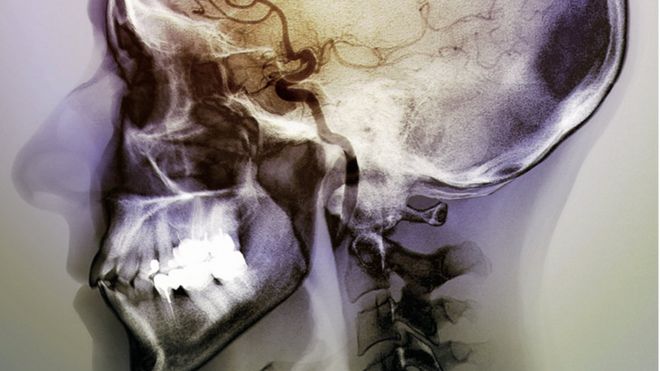

The insular cortex lies deep in the brain and has widespread connections to surrounding regions.

Experts believe its primary role is to do with desires and emotions.